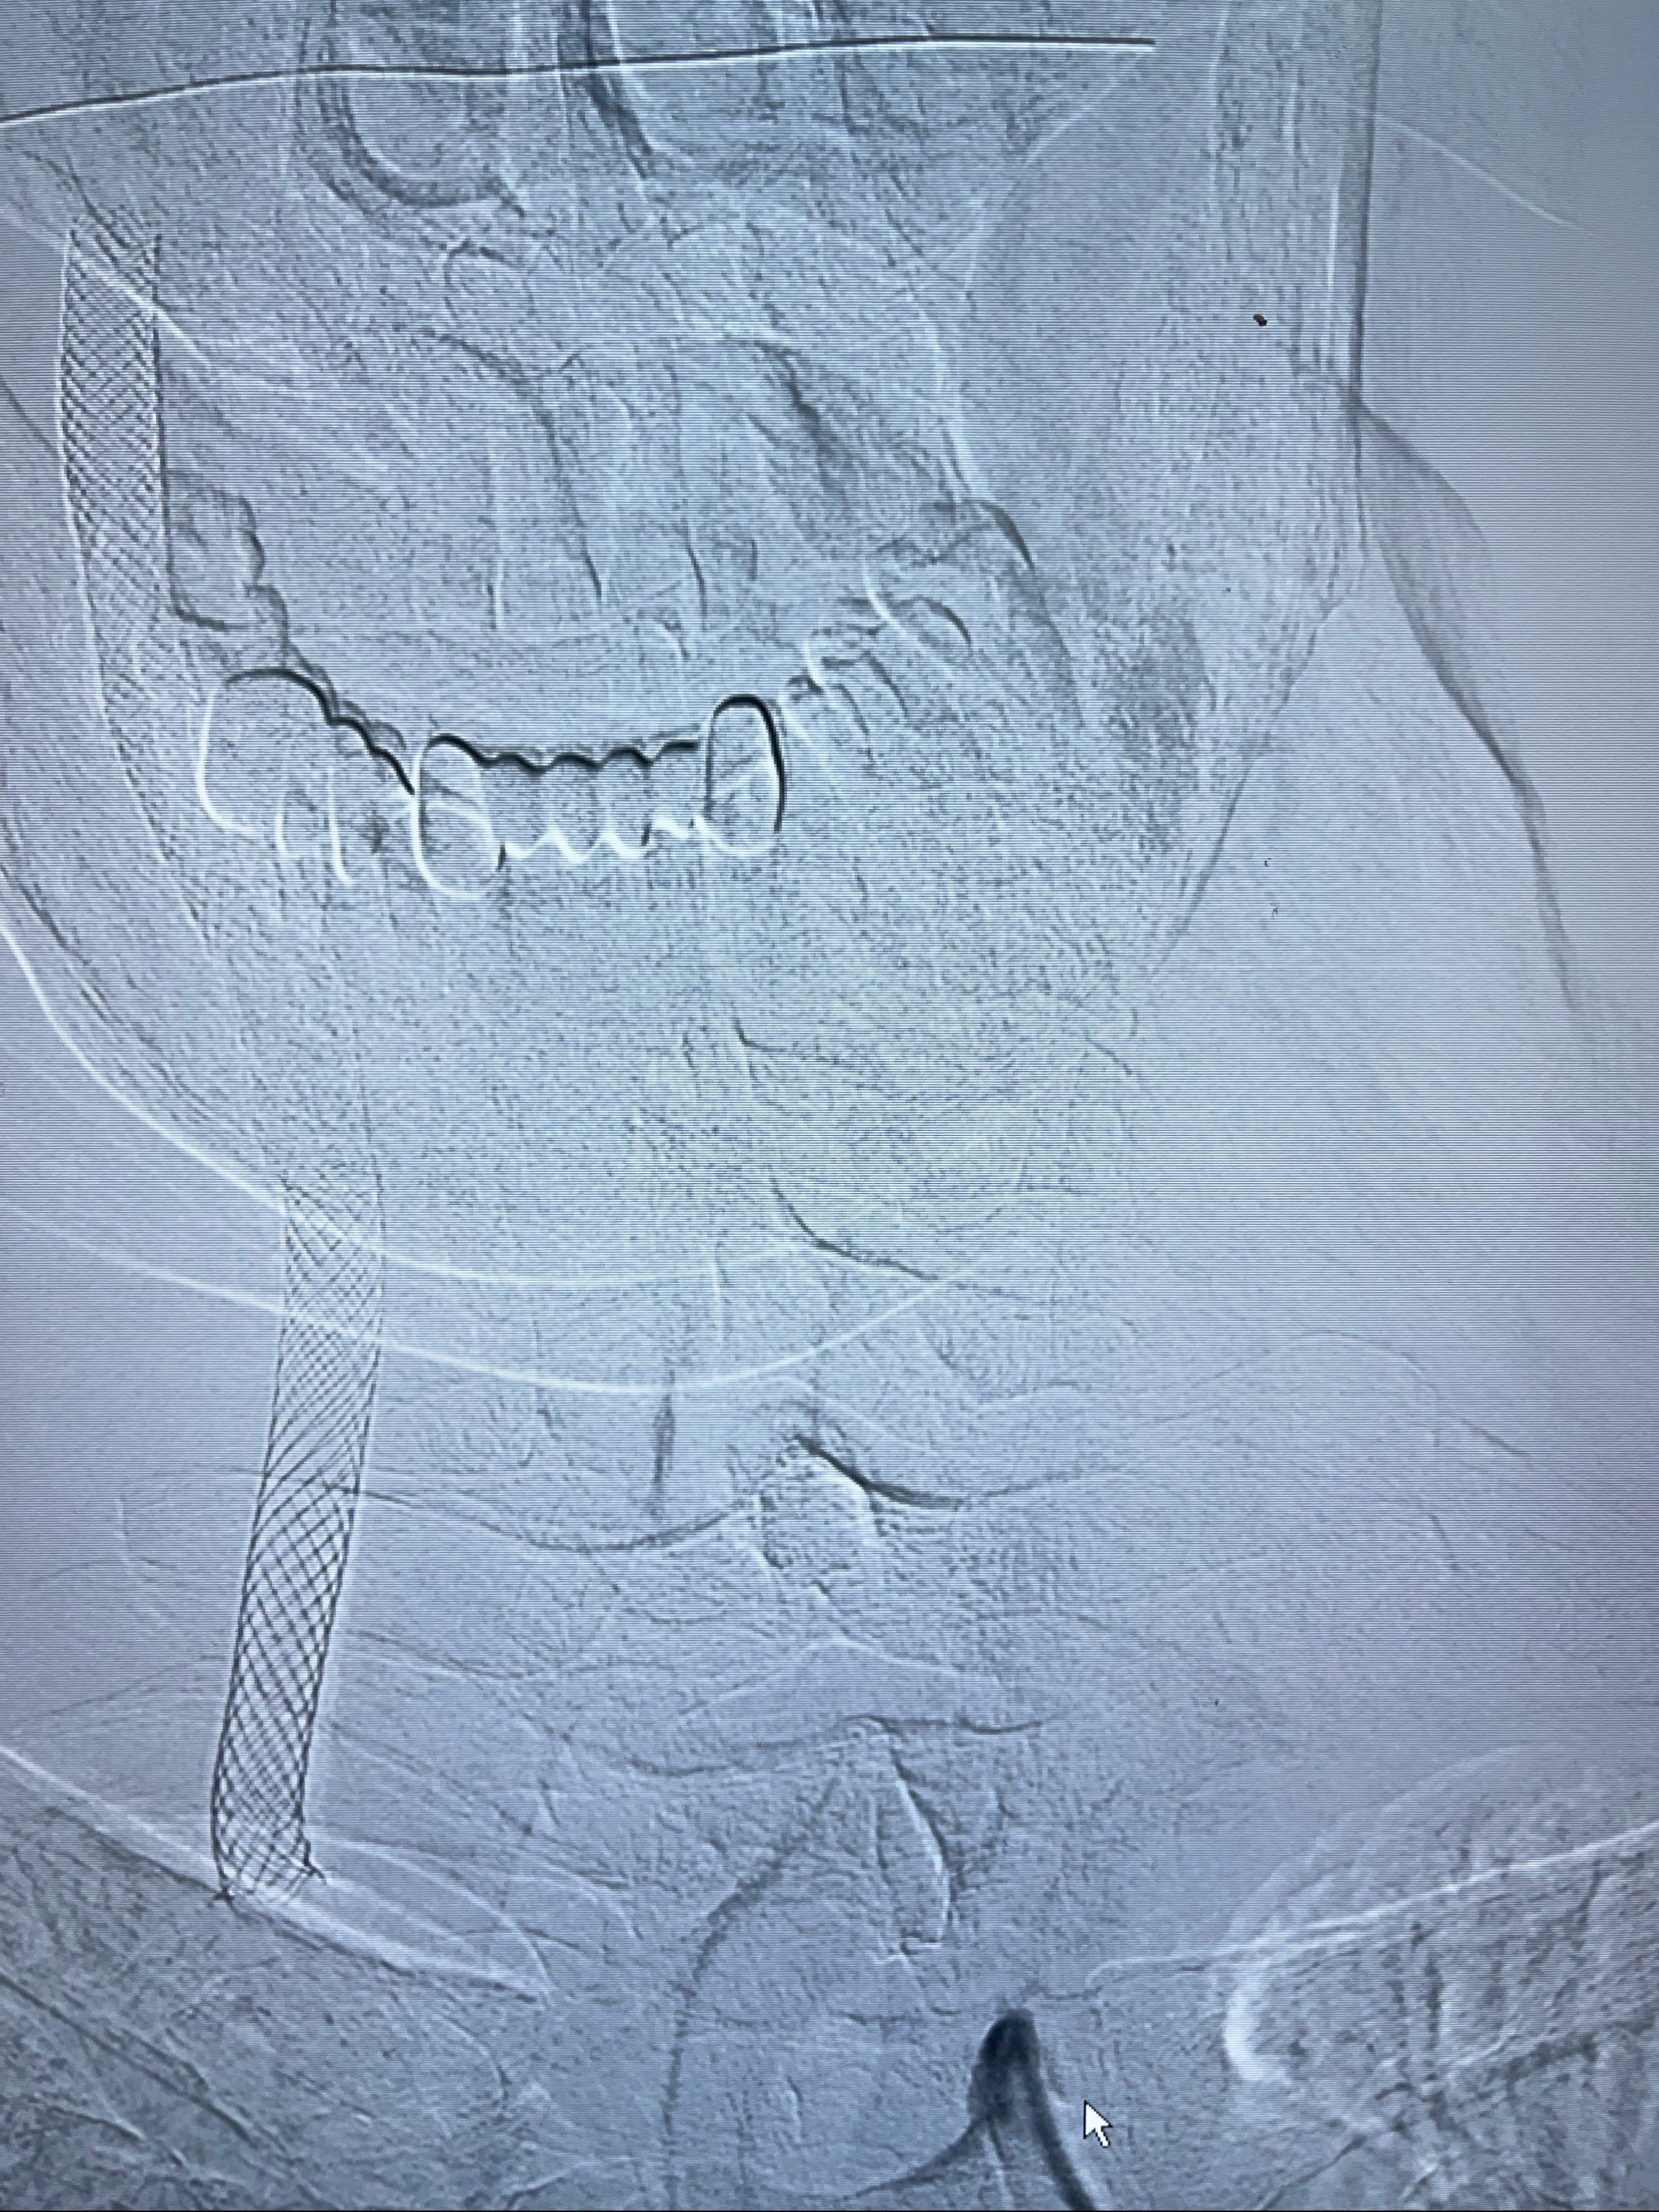

重新行“路径图”,支架导管在微导丝引导下超选择性插入至右侧颈内动脉眼段,4.5-50mmLeo支架释放,远心端位于海绵窦段,近心端位于岩骨段狭窄段以近

即刻造影显示支架贴壁佳

路径图下,5.5-50mmLeo支架导管在微导丝引导下超选择性插入远段Leo支架内

两枚支架部分重叠

多次确认支架位置及打开贴壁情况

支架完全打开,近心端位于原颈动脉支架远心端内